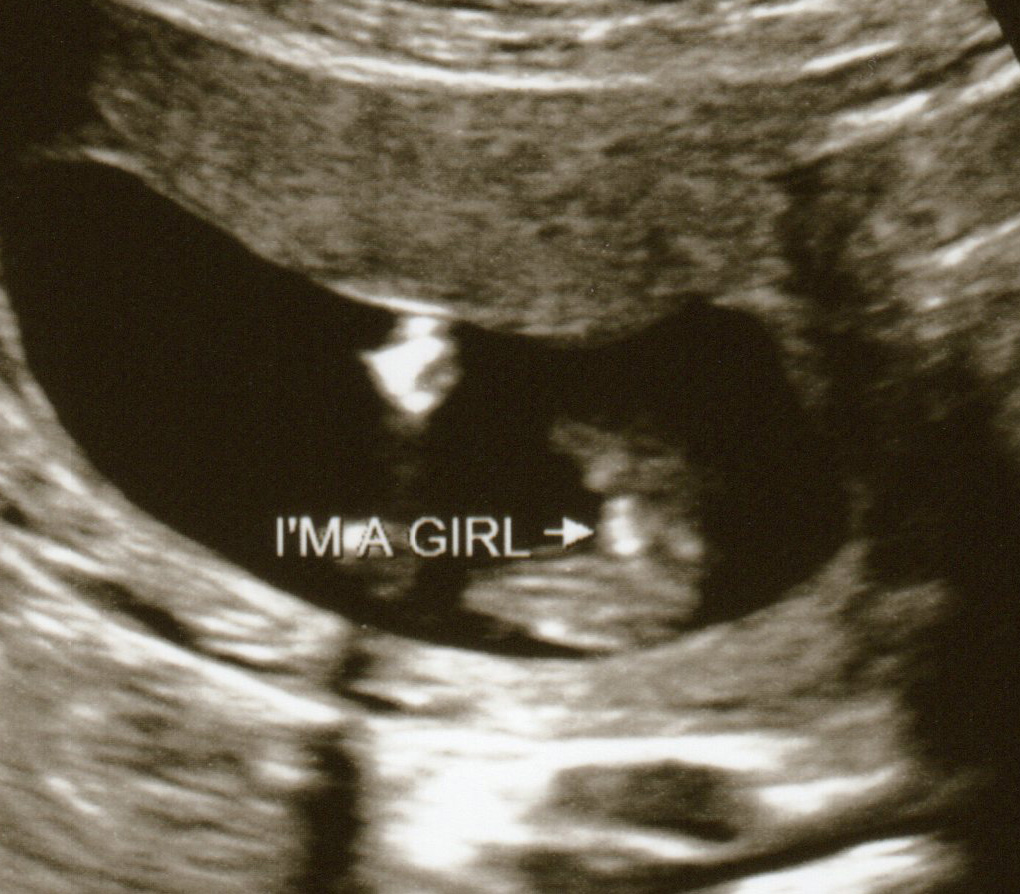

Confirmed girl, nub shots from 11 & 12 weeks, potty shots from 13 & 15 weeks

Confirmed girl by amniocentesis. So excited to be adding another sweet daughter to our family! I hope these pics are helpful - I know I was looking all over for pics to compare to before we found out with certainty.

Potty shot at 15w1d:

Attachment 3215